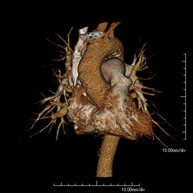

- Angio-TC Cardíaco o TC Cardíaco El angio-TC Cardíaco o Coronariografía no invasiva es una prueba diagnóstica que consiste en el estudio de las arterias del corazón o arterias coronarias mediante el empleo de un equipo de TC Multidetector de última generación y de un contraste yodado, obteniendo imágenes bi y tridimensionales. El TC Multidetector o TCMD permite una adquisición de imágenes tan rápida, que se pueden valorar las arterias coronarias con una alta precisión anatómica: estrechamientos o estenosis, calcificaciones, variantes anatómicas, etc., ya que gracias a su rapidez evita el artefacto que provoca el movimiento constante del corazón (tarda menos de diez segundos en adquirir unas 1000 imágenes). La información obtenida precisa de un tratamiento en estaciones de trabajo con programas especializados en la reconstrucción de las arterias coronarias que permiten valorar el número, la localización y las características de las lesiones. Toda esta información se obtiene de manera no invasiva: solo se requiere la punción de una vena periférica (en el brazo). Es necesario que la frecuencia cardíaca no supere los 75 latidos por minuto, por lo que algunos pacientes deberán realizar un tratamiento previo con un fármaco betabloqueante. El angio-TC Cardíaco o Coronariografía no invasiva es una prueba diagnóstica que consiste en el estudio de las arterias del corazón o arterias coronarias mediante el empleo de un equipo de TC Multidetector de última generación y de un contraste yodado, obteniendo imágenes bi y tridimensionales. El TC Multidetector o TCMD permite una adquisición de imágenes tan rápida, que se pueden valorar las arterias coronarias con una alta precisión anatómica: estrechamientos o estenosis, calcificaciones, variantes anatómicas, etc., ya que gracias a su rapidez evita el artefacto que provoca el movimiento constante del corazón (tarda menos de diez segundos en adquirir unas 1000 imágenes). La información obtenida precisa de un tratamiento en estaciones de trabajo con programas especializados en la reconstrucción de las arterias coronarias que permiten valorar el número, la localización y las características de las lesiones. Toda esta información se obtiene de manera no invasiva: solo se requiere la punción de una vena periférica (en el brazo). Es necesario que la frecuencia cardíaca no supere los 75 latidos por minuto, por lo que algunos pacientes deberán realizar un tratamiento previo con un fármaco betabloqueante.

- Score cálcico Prueba diagnóstica que consiste en la medición de la cantidad de calcio que puede haber acumulado en las placas de ateroesclerosis de las arterias coronarias mediante el empleo de un equipo de TC Multidetector de última generación. Es una prueba no invasiva que no requiere contraste yodado. No necesita preparación previa. La detección de las placas calcificadas se realiza en una estación de trabajo especializada que permite la cuantificación exacta de la cantidad de calcio dando una puntuación, que es lo que en la práctica médica se llama Score Cálcico. Prueba diagnóstica que consiste en la medición de la cantidad de calcio que puede haber acumulado en las placas de ateroesclerosis de las arterias coronarias mediante el empleo de un equipo de TC Multidetector de última generación. Es una prueba no invasiva que no requiere contraste yodado. No necesita preparación previa. La detección de las placas calcificadas se realiza en una estación de trabajo especializada que permite la cuantificación exacta de la cantidad de calcio dando una puntuación, que es lo que en la práctica médica se llama Score Cálcico.